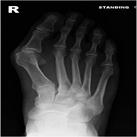

Symptoms include pain in the bump area with or without shoes and occasionally associated discomfort in the ball of the foot (metatarsalgia) and/or lesser toe deformities (Fig 2) such as a hammertoe from direct pressure of the big toe. The diagnosis is confirmed by clinical assessment and x-rays (Fig 3).